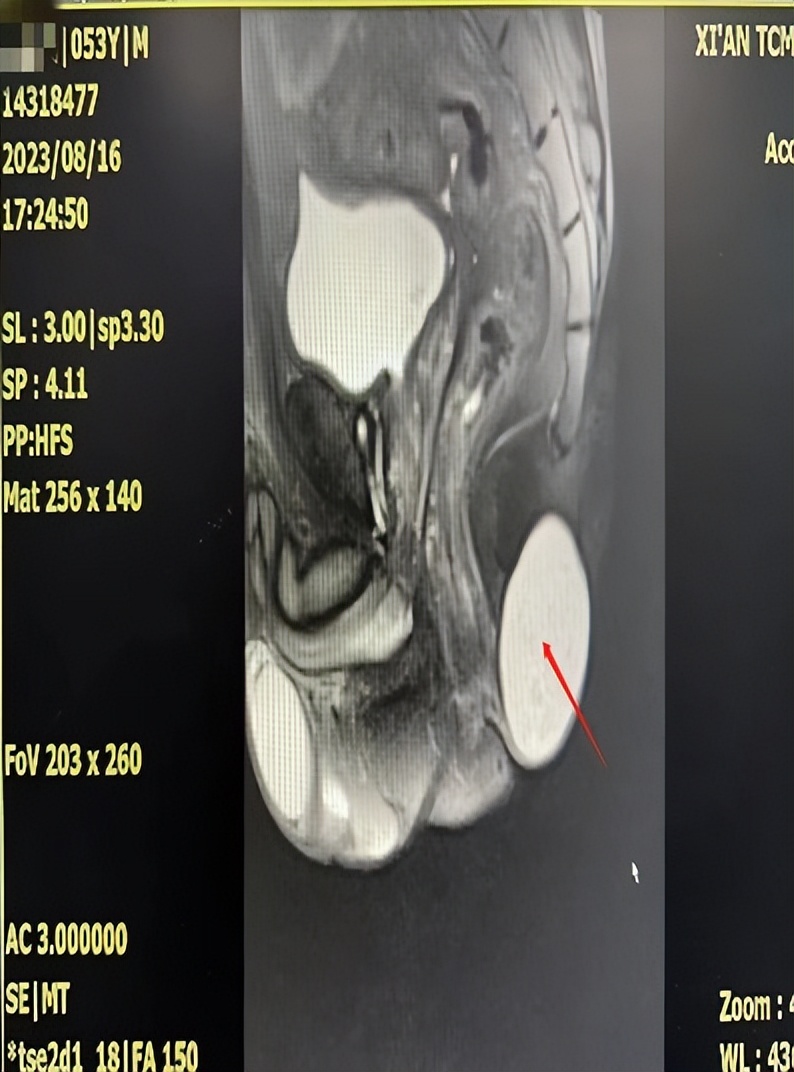

术前肛周MRI资料

孙林梅主任医师为患者进行专科检查时发现其肛旁6点位骶尾部中线处有大小约6cm×8cm的皮肤肿胀,略发红,表面无溃破口;按压骶尾部肿物皮温正常,质地柔韧,呈囊性感,活动度良好,无压痛,伴有憋胀不适。肛肠超声提示:考虑皮脂腺囊肿。肛周磁共振提示:尾椎下方囊性病灶,考虑表皮样囊肿,其前方线状信号影,考虑小血管影可能,必要时DWI进一步检查。结合病史、查体及辅助检查,孙林梅主任医师凭借丰富的临床经验为患者安排住院手术以解除病痛。

患者入院后主管大夫宋磊副主任医师询问病情、仔细查体,对比肛肠超声、肛周MRI,查看化验结果,在孙林梅主任医师指导下制定更优的个体化手术治疗方案。